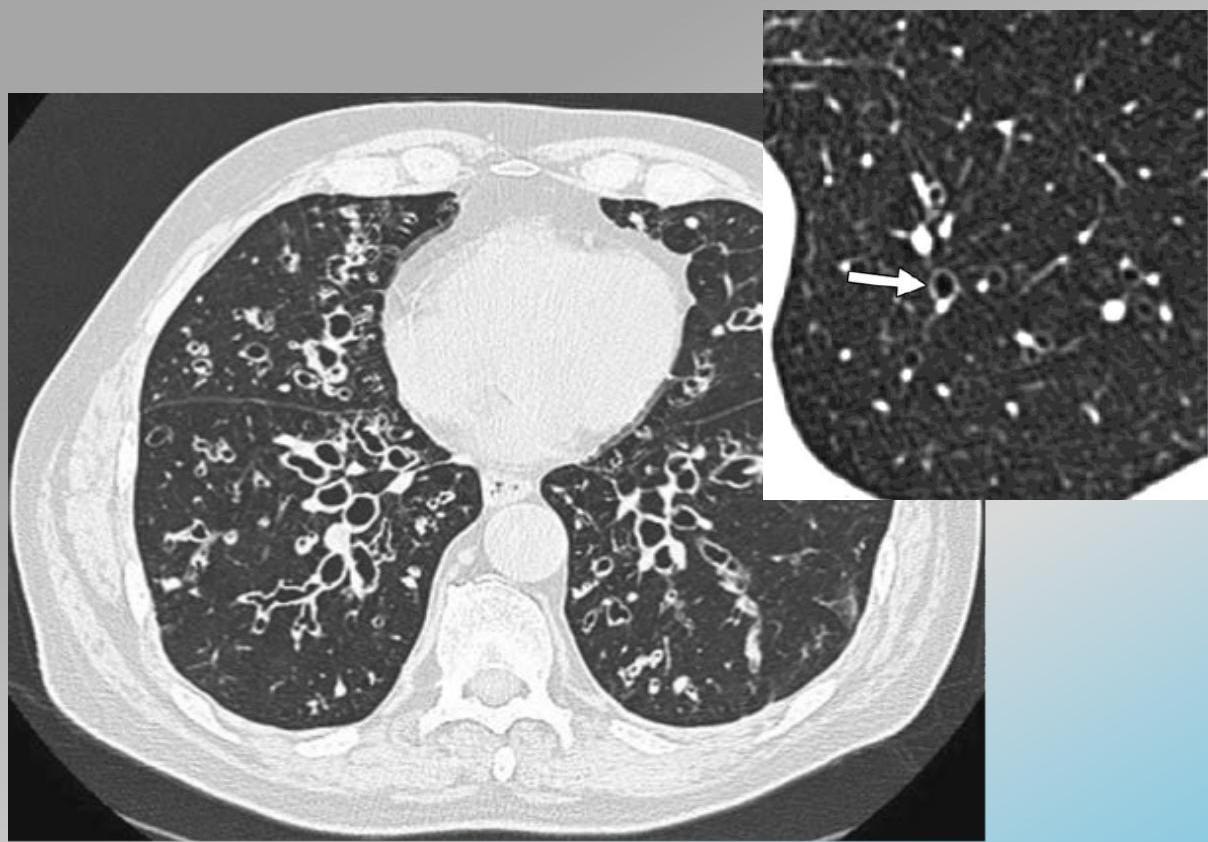

Signet Ring Appearance

CT scan showing bronchiectasis. Note the dilated bronchi with thickened wall, which are larger than adjacent arteries, giving a signet ring appearance.